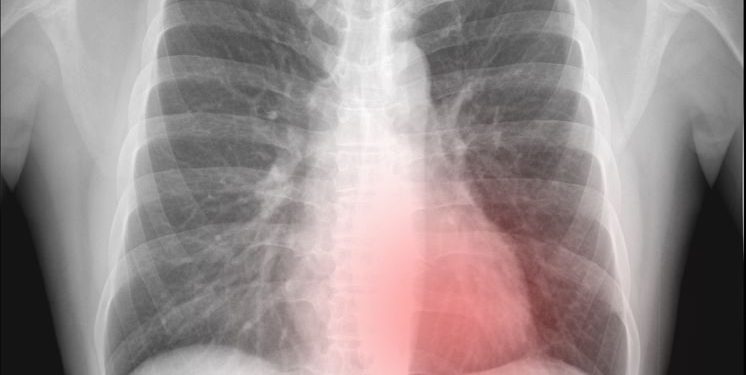

When a person has a small pneumothorax, the air will probably go away on its own. However, it may take several days before a person realizes that something is wrong. It can also be difficult to diagnose. Most doctors diagnose pneumothorax using a chest X-ray. They also listen to the person’s breathing through a stethoscope. In other cases, a doctor may use a special light probe to look inside the person’s chest for an air leak. This is faster than using an X-ray and can be less painful for the patient.